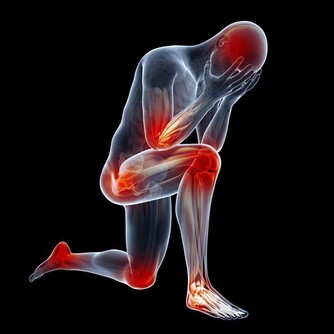

3.局部疼痛:如肛周、下腹部甚至睾丸脹痛。前列腺炎的預防措施很簡單,從病因出發,即可有效預防。